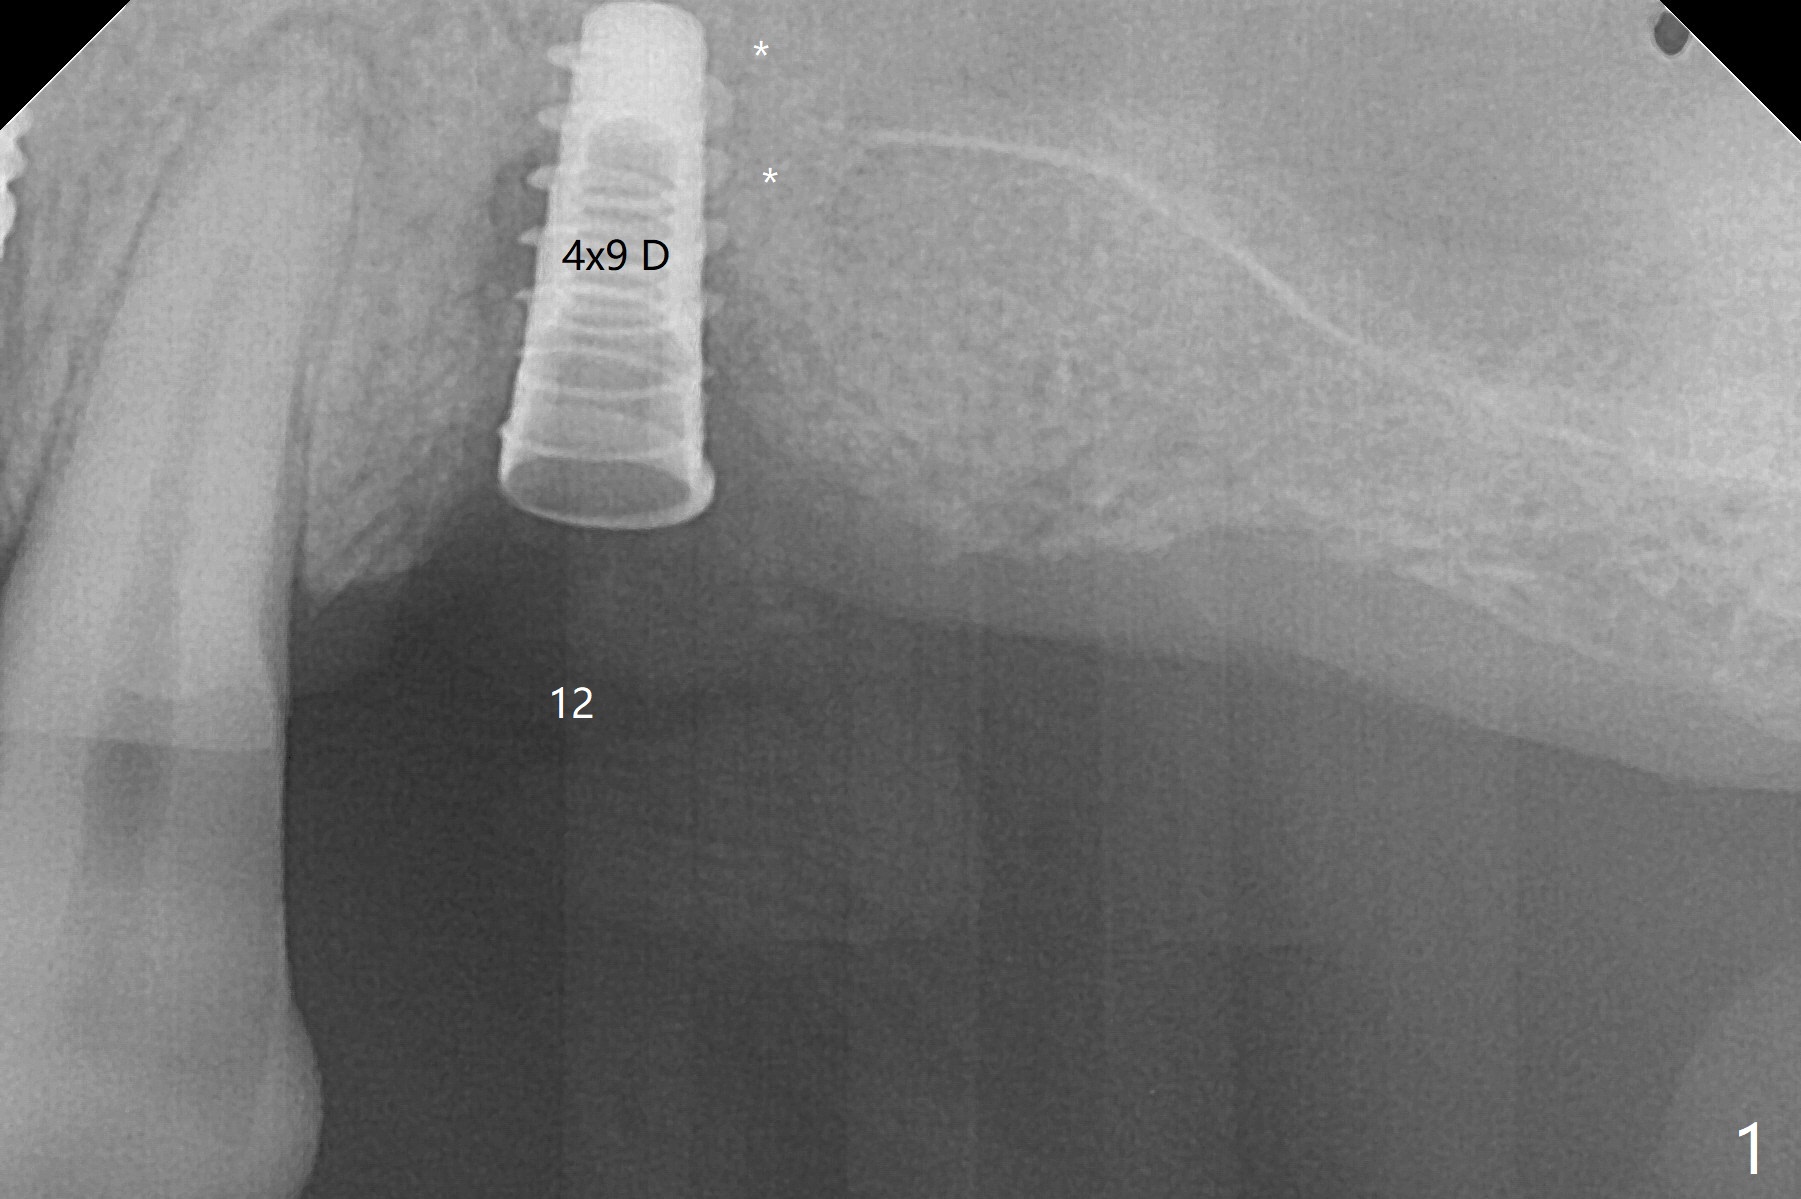

Five months post implant removal and bone graft, incision is made at #12. Osteotomy is being done with guide until 3.0x7.3 mm drill with 1 O-ring (palatal wall being thin), followed by 3.2x17-19 mm sinus round drills and 2.2x11.5 mm drill. After placement of 2 small loads of bone graft, a 4x9 mm dummy implant is inserted for sinus lift (Fig.1,2 *). By this time, the buccal plate is gone, while there is apparently the palatal periosteum. With more bone graft for sinus lift, a 4x9 mm final implant is placed with 30 Ncm (machine) and 4 mm subgingival (Fig.3,4 double arrows). Sticky bone (Fig.5,6 *) is applied around the coronal end of the implant and cover screw (S), followed by 2 pieces of PRF and 4-0 PGA suture. The sutures appear to have been dissolved and PRF membrane exposed 7 days postop (Fig.7,8 (smoker)). Four months postop, the wound heals except a small hole, which seems to be communicated with the underlying implant (Fig.9). The sinus lift remains (Fig.10 <), while bone loss appears to be present around the implant (Fig10,11 *). After placement of 5.5x4 mm healing abutment and before suturing, allograft is pushed into periimplant space (Fig.12, 13 *).